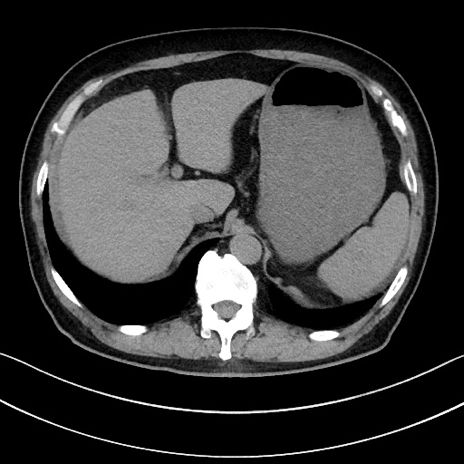

冠状断像

【症例】70歳代男性

【主訴】腹痛

【現病歴】今朝から腹痛あり。全体的に痛い。特に左上の方。排ガスが今日はない。冷や汗が出る。

【既往歴】直腸癌術後

【身体所見】左側腹部〜上腹部に圧痛あり。腹膜刺激症状明らかなではない。軽度反跳痛。左下腹部に術後瘢痕あり。

【データ】WBC 7700、CRP 0.02